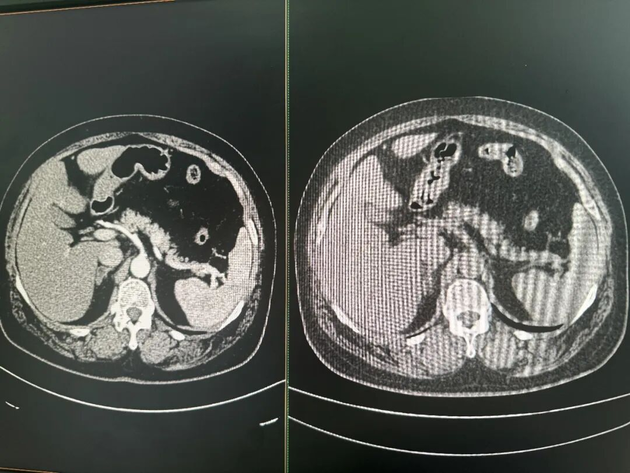

Dr. Zhu explained that clinically, abdominal CT scans are divided into non-contrast and enhanced CT. Enhanced CT requires patients to receive contrast agents, providing clearer images of organs and lesions, but it is more costly, complex to perform, and carries a risk of allergic reactions—typically reserved for patients with specific diagnostic needs.

Comparison of contrast-enhanced CT (left) and non-contrast CT (right) images Photo/Zheng Yuhang (NBD)

In contrast, non-contrast CT is affordable and widely used, serving as one of the most common imaging tools in routine physical exams and outpatient visits.

However, due to the low contrast between the pancreas and surrounding tissues, it is difficult to visualize on non-contrast CT scans. Tiny early-stage tumors are practically "invisible" and extremely hard to detect with the naked eye. Thus, "non-contrast CT cannot be used for early pancreatic cancer screening" was once a universal consensus among radiologists.